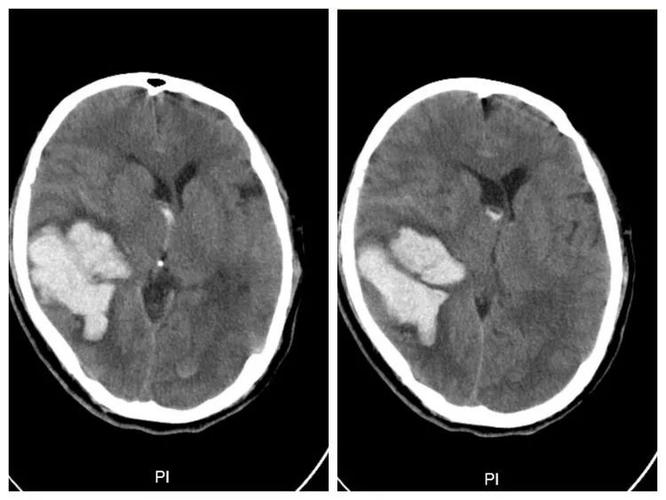

脑叶出血

脑叶出血约占脑出血的13%~31%,国内报道占17.3%.

> 内科 > 神经内科 > 脑出血 > 概况 3,脑叶出血:也称为皮质下白质